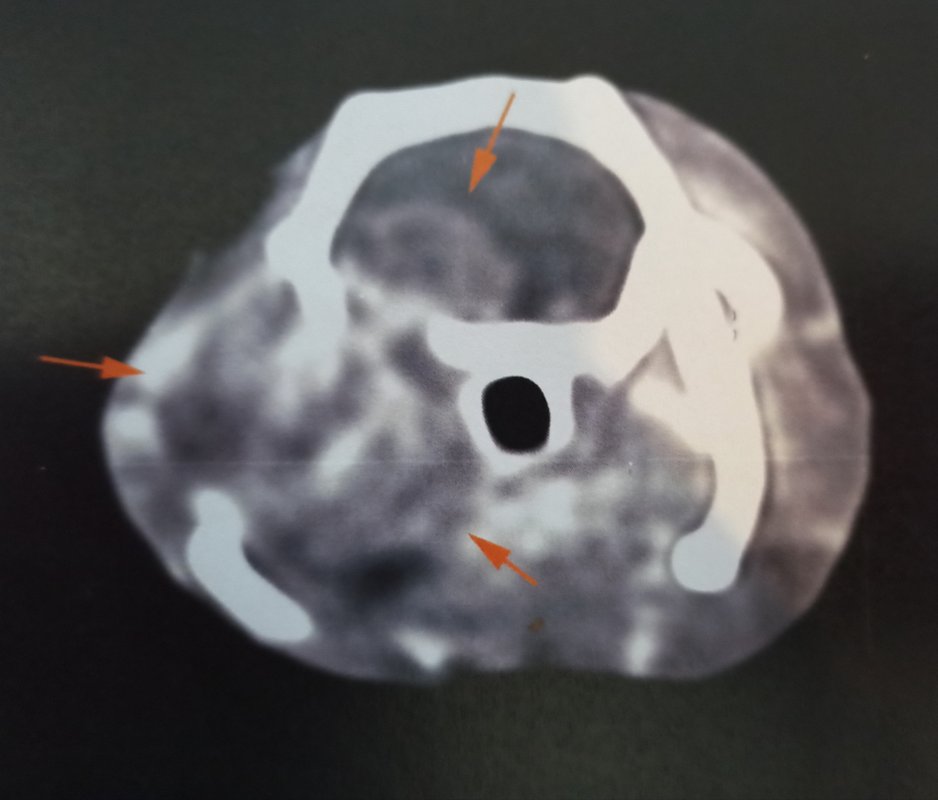

Alors figurez-vous que... C'est une otite ! Mais ce n'est pas réjouissant pour autant :|

J'ai finalement accepté le scanner, ça a été fait aujourd'hui, ils l'ont gardé la nuit d'avant et en ont profité pour le requinquer en nourriture et le réhydrater pour qu'il soit autant en forme que possible pour l'anesthésie.

Quand je l'ai amené hier, la véto m'a dit que si le produit de contraste est correctement injecté, normalement on ne devrait pas rater une éventuelle TH (sauf si toute toute petite mais dans ce cas peu probable que ce soit ça le problème). J'y connais à peu près rien en imagerie médicale, mais peut être que la largeur de coupe dépend aussi de la machine de la clinique ? Dans ce papier, ils ont fait passer un scanner avec injection de produit de contraste à 25 rats présentant des symptômes de TH, et ils ont pu voir une tumeur chez 20 d'entre eux. Pour les 5 autres ils parlent d'otite mais j'ai pas vraiment compris si le diagnostic avait été confirmé.

D'après son expérience, en cas de troubles neurologiques chez le rat, lorsqu'ils font un scanner elle estime qu'ils trouvent environ 1/3 d'otites et 2/3 de TH. Elle a reconnu qu'il n'avait pas tous les symptômes habituels de l'otite, mais elle ne voulait pas l'exclure, car parfois ça peut être un peu atypique.

Et effectivement, pour le coup c'était ça. On ne le voit pas de l'extérieur mais il y a un gros gonflement autour de la bulle tympanique, c'est ça qui a décalé sa mâchoire en fait, et malheureusement cela a également atteint le cerveau...

Une chirurgie est possible pour la partie hors du cerveau, ce qui pourrait permettre de le rendre plus confortable pour manger, mais ce n'est pas sans risque d'empirer les choses, et quoi qu'on fasse on n'a pas d'espoir de guérison, seulement de lui faire gagner un peu de temps en gérant au mieux douleur et inconfort. Elle m'a fait une prescription de tramadol à ajouter au reste s'il semble avoir mal.

Je vous partage les images parce que vu le prix qu'elles m'ont coûtées autant que tout le monde en profite ><